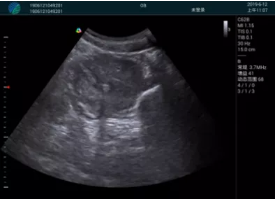

病例一:

清晰顯示孕囊,通過軟件包計算孕齡7w+6d

M20實時引導(dǎo),術(shù)中清晰顯示孕囊被破壞和抽吸針的過程,清晰顯示吸引針

抽吸結(jié)束后縱切子宮,孕囊已被完全抽吸,未見明顯殘留

橫切子宮,發(fā)現(xiàn)右側(cè)宮腔靠近宮角處有少許脫模樣殘留

M20引導(dǎo)下,抽吸針找到右側(cè)宮角處再次清掃

二次抽吸后再次進行超聲檢查,宮腔未見殘留,宮腔線清晰顯示

超聲引導(dǎo)下可視化人流是技術(shù)安全性的保障,一般對人流術(shù)設(shè)備預(yù)算不高,M20具備婦產(chǎn)科軟件包,且穿透力圖像質(zhì)量好,既滿足人流引導(dǎo)需要,也可用于床旁超聲的需求。